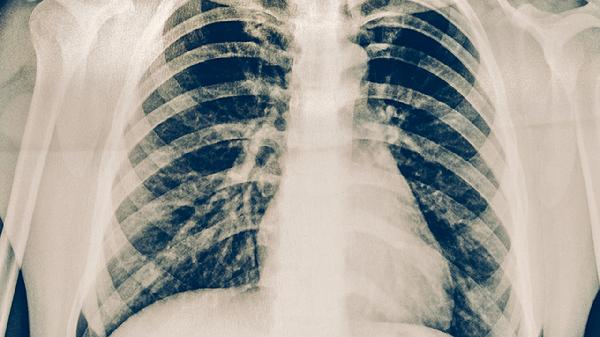

肋骨骨折可遵医嘱使用双氯芬酸钠凝胶、氟比洛芬凝胶贴膏、云南白药气雾剂、活血止痛膏、消痛贴膏等外用药物辅助缓解疼痛和肿胀。肋骨骨折通常由外伤、骨质疏松等因素引起,表现为局部疼痛、呼吸受限等症状,需结合影像学检查确诊。